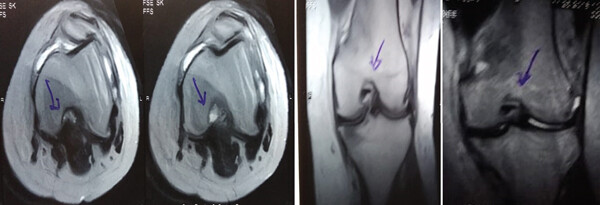

MRI:治療前后的MRI結(jié)果

治療前 MRI 顯示內(nèi)側(cè)和外側(cè)半月板后角 III 級撕裂。

治療后MRI檢查顯示內(nèi)側(cè)和外側(cè)半月板后角撕裂有所改善。患者癥狀改善,日常生活活動能力增強(qiáng)。

結(jié)論:間充質(zhì)干細(xì)胞治療后,MRI檢查顯示內(nèi)側(cè)和外側(cè)半月板后角撕裂有所改善 ,關(guān)節(jié)功能也有改善,未出現(xiàn)嚴(yán)重不良事件。可以達(dá)到干細(xì)胞治療半月板損傷短期療效的目標(biāo)。